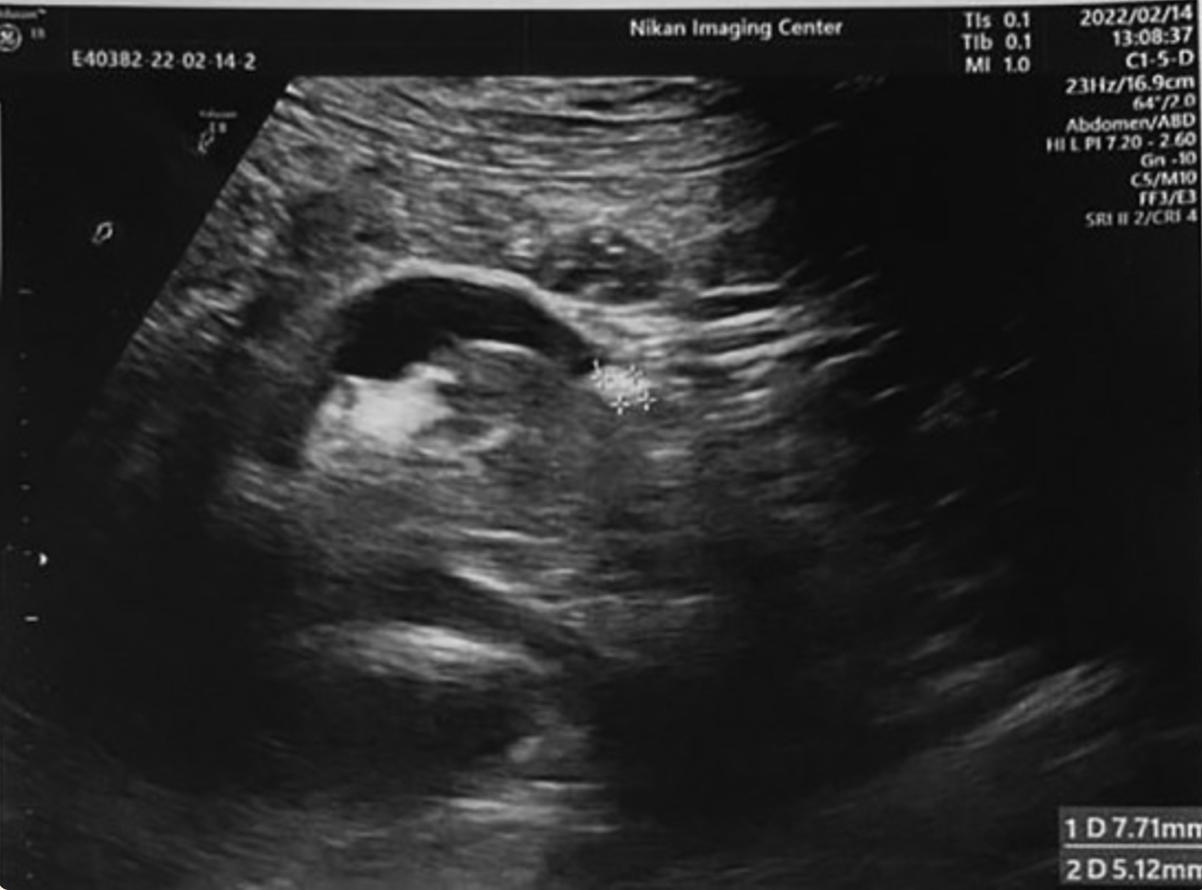

肾脏超声检查结果显示一个清晰的圆形异回声固体肿物(52 × 51 mm),在右肾中极向肾外延伸 (103mm),压迫肾窦。左肾旋转不良,位于正常解剖部位的尾部(图1)。随后,腹部和骨盆螺旋计算机断层扫描(CT)和腹部磁共振成像(MRI)显示 右肾中极50× 53 × 48 mm肿物,影响邻近右肝叶的肾盂输尿管系统,提示肾细胞癌(RCC),以及左输尿管近端一4mm结石,距离HK左侧肾盂输尿管连接处21mm(图2和3)。肾结石类型为草酸钙。在此之前,患者没有意识到自己的肾脏异常,也没有观察到任何泌尿系统相关症状。

图1 肾脏超声检查;左输尿管近端结石引起的左肾旋转不良伴盆腔充盈